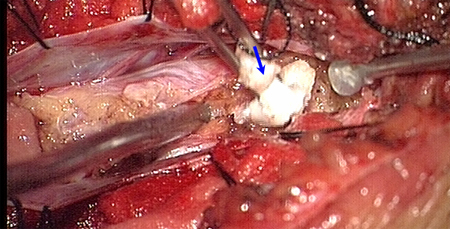

术中发现L4-5椎板异常增生肥厚,L5椎板伸入椎管内形成骨嵴,脊髓圆锥低位在L4水平,L4以下肿瘤组织为多种成份,近端为脂肪组织,S1水平分为两种肿瘤成份,内侧为清亮粘液状物、外侧为珍珠样角化物。

术后病理结果为成熟性囊性畸胎瘤。术后图片